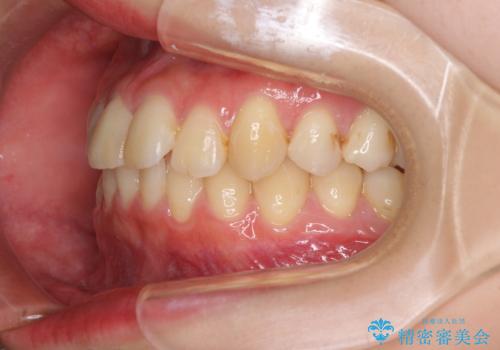

- 上下前歯のデコボコを気にして来院された患者様です。

以前矯正をした後戻りということで、歯列不正はそれほど大きくなかったため、インビザライン・ライトを用いて矯正治療を行うこととしました。

前歯のデコボコが残っており、シミュレーション通りに動いていない部分がありましたが、再矯正であることやご本人の満足いくところまでデコボコが改善されたとのことで、治療を終了することとしました。